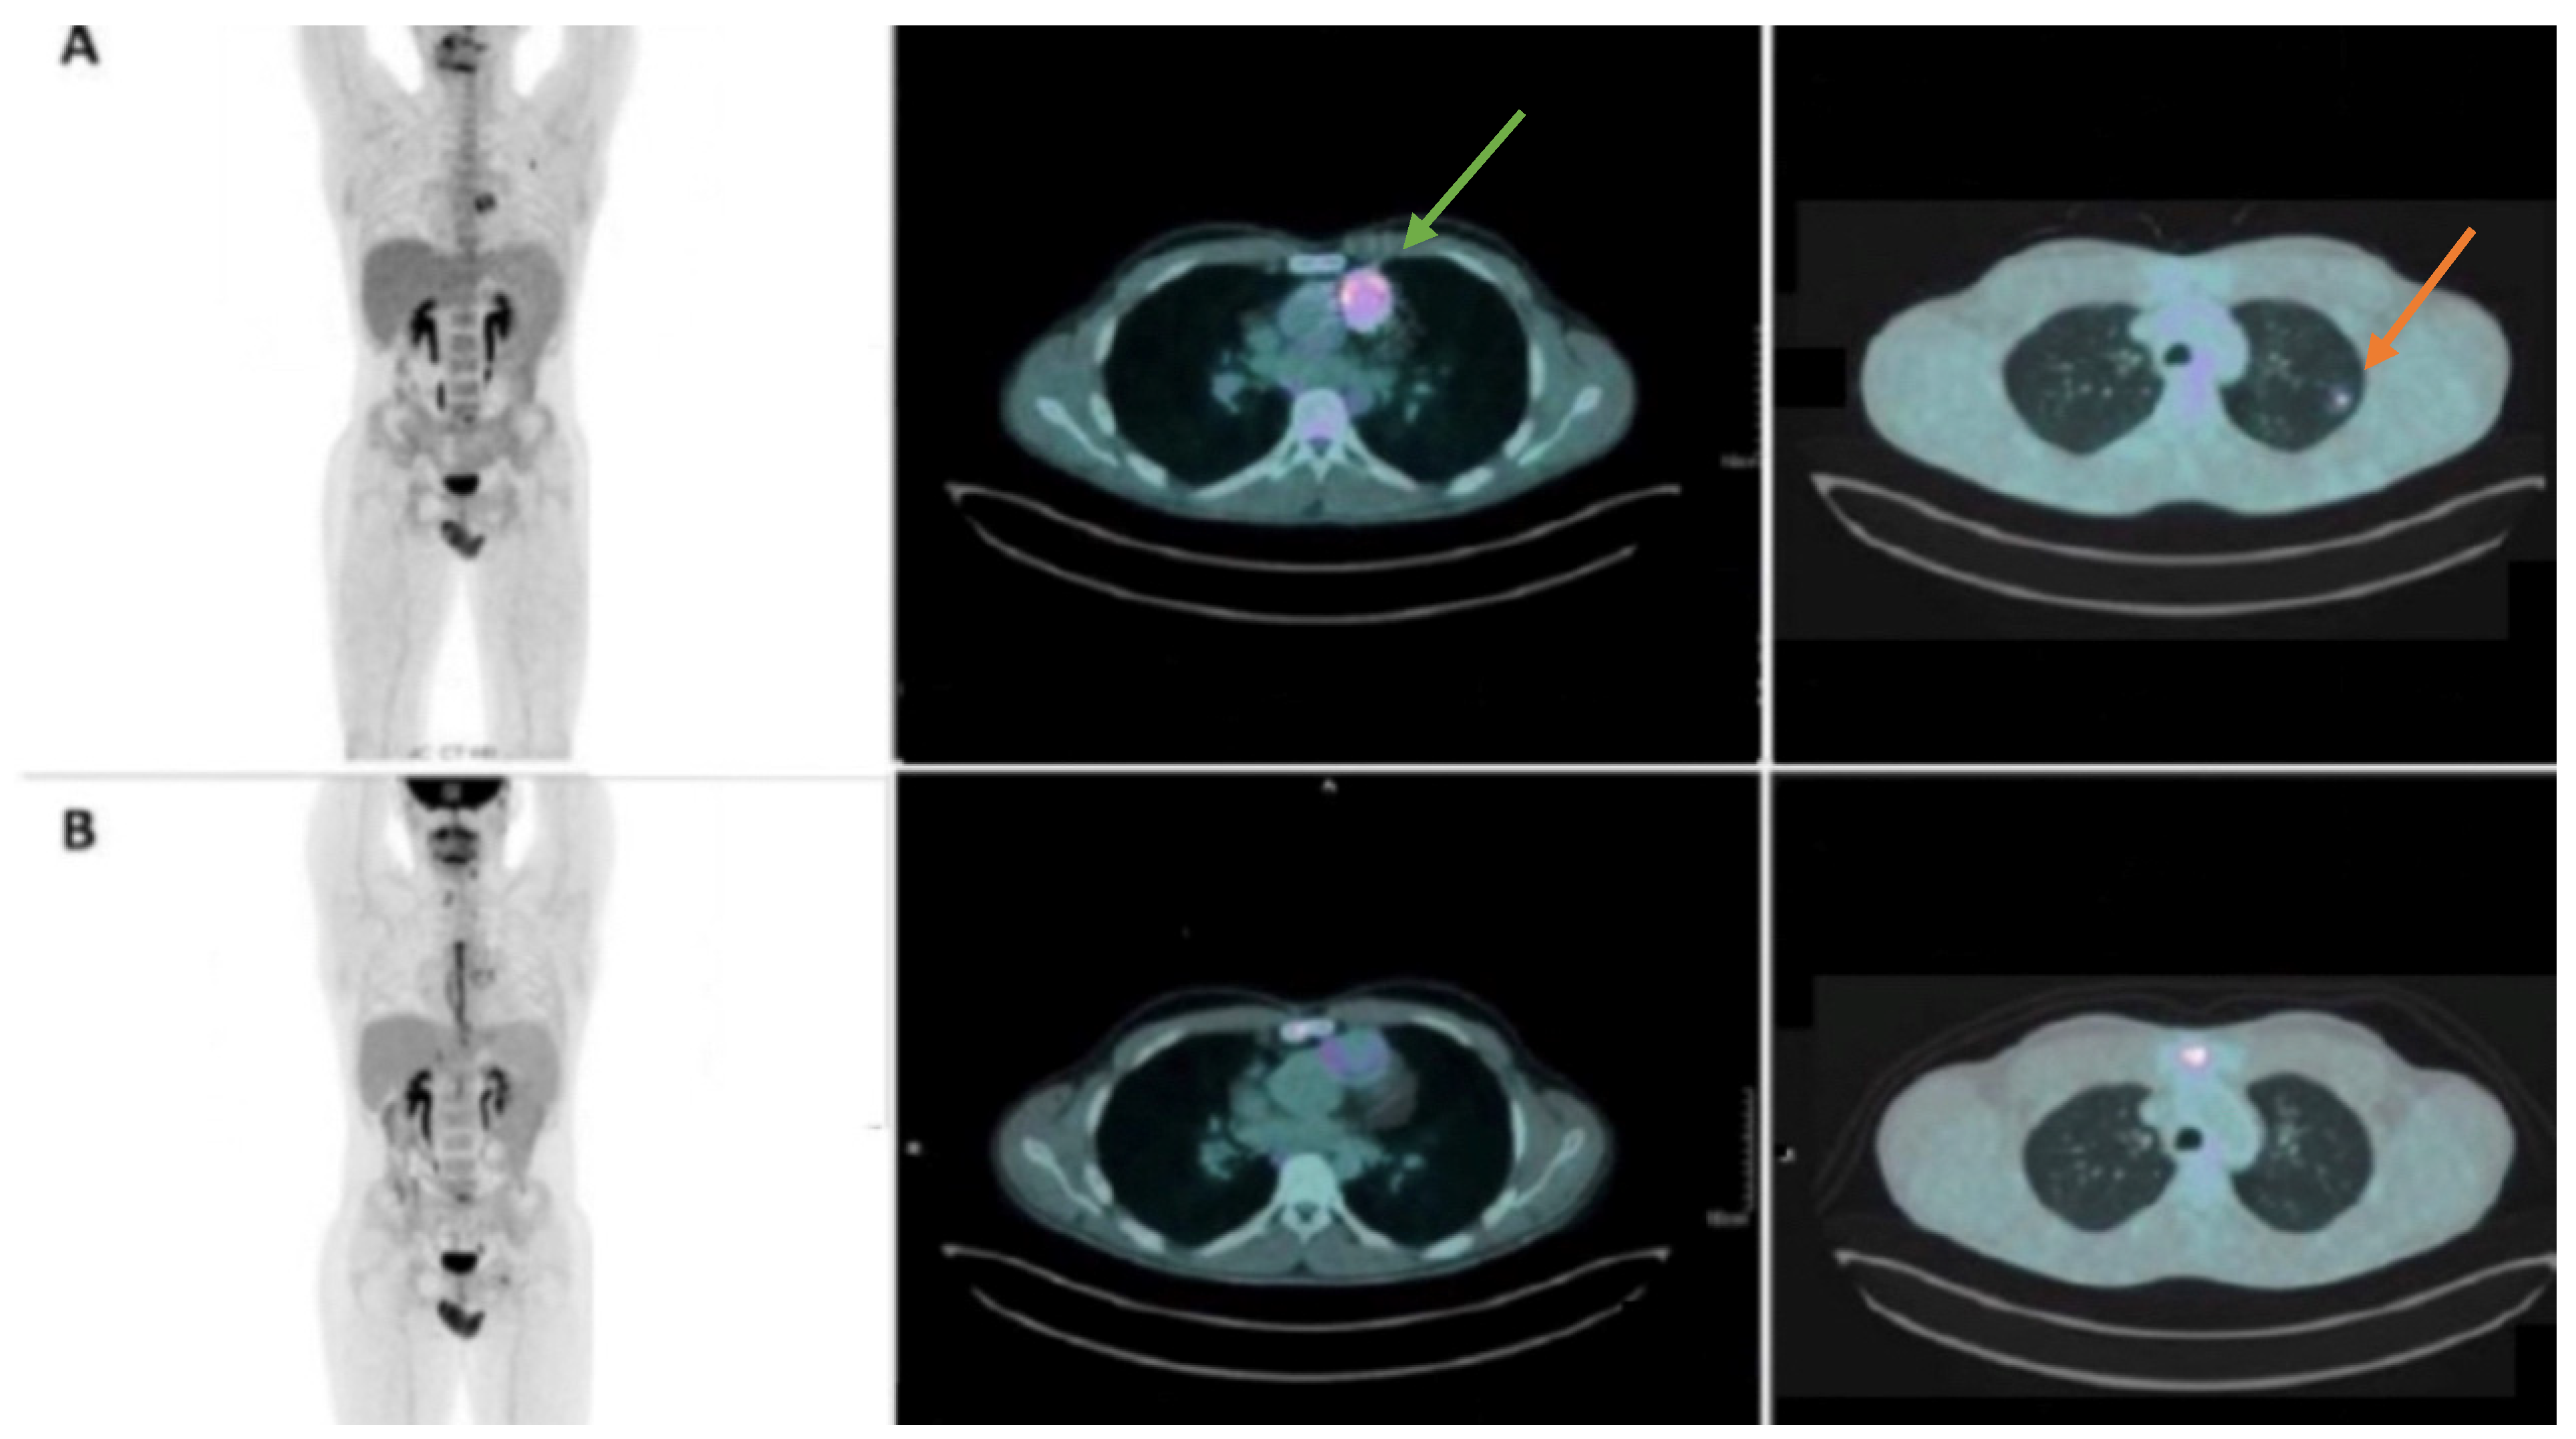

- Caobelli, F.; Kamani, C.H.; Nkoulou, R.; Buechel, R.R. Executive Committee of the Swiss Society of Nuclear Medicine (SGNM) The importance of 18F-FDG cardiac PET/CT for the assessment of myocardial viability in ischaemic heart disease. Swiss Med. Wkly. 2021, 151, w20511. [Google Scholar] [CrossRef]

- Meyer, Z.; Fischer, M.; Koerfer, J.; Laser, K.; Kececioglu, D.; Burchert, W.; Ulrich, S.; Preuss, R.; Haas, N. The role of FDG-PET-CT in pediatric cardiac patients and patients with congenital heart defects. Int. J. Cardiol. 2016, 220, 656–660. [Google Scholar] [CrossRef]